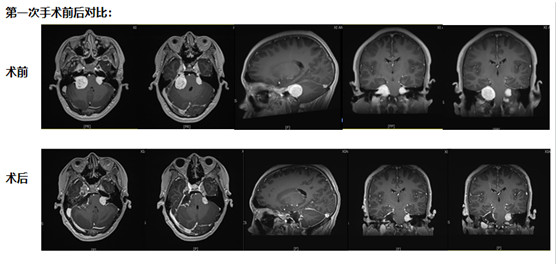

第一次手術(shù):從耳后開(kāi)口,既要拆瘤又要保聽(tīng)力

考慮到小倪才21歲,團(tuán)隊(duì)沒(méi)選 “一刀切” 的方案,而是決定從耳后開(kāi)一個(gè)約10厘米的小口 ——這個(gè)位置能精準(zhǔn)摸到耳朵旁邊的腫瘤,還能盡量避開(kāi)控制聽(tīng)力、面部活動(dòng)的神經(jīng)。

手術(shù)當(dāng)天,醫(yī)生在顯微鏡下一點(diǎn)點(diǎn) “剝” 腫瘤:剝到腫瘤深處時(shí),醫(yī)生發(fā)現(xiàn)再往里切,必然會(huì)傷著聽(tīng)力神經(jīng)。“停!這里留一點(diǎn)點(diǎn),先保聽(tīng)力。”團(tuán)隊(duì)果斷調(diào)整,把能安全切除的腫瘤全清干凈,再仔細(xì)止血,避免術(shù)后出血。